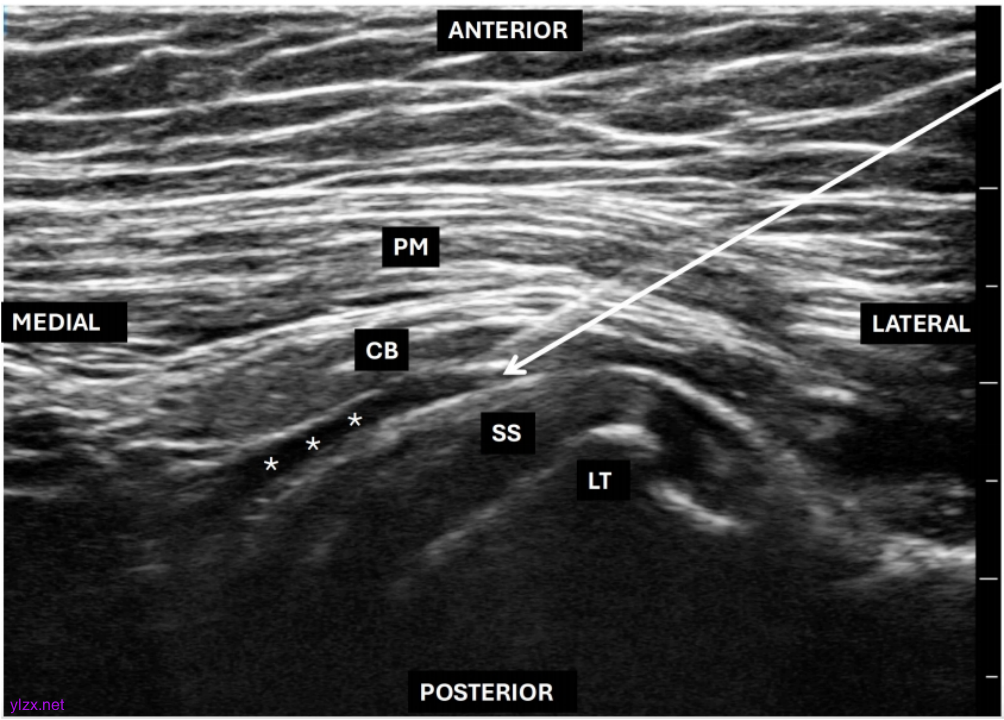

基于以上解剖学基础,一种靶向腋神经和肩胛下神经的新的超声引导入路应运而生。如图1所示,该入路将超声探头水平定位于喙突下间隙,手臂外展60-90度,肱骨外旋。外展和外旋动作将肩胛下肌拉至超声更容易观察的平面,示清喙突与手臂之间的喙肱肌纵向平面,同时该体位可示清胸大肌、喙臂肌、肩胛下肌和肱骨小结节等关键标志。

图1 目标靶点喙肱肌-肩胛下肌平面(CBSS)位于喙肱肌(CB)与肩胛下肌(SS)之间,用“***”表示;白色箭头:穿刺针轨迹;LT:肱骨小结节;PM:胸大肌。

这三层肌肉平面的厚度因人而异,因此首先识别肱骨及其上方的肩胛下肌,随后定位其浅表平面。阻滞针从外侧向内侧进针,穿入喙肱肌深层和肩胛下肌浅层之间的平面,可同时阻滞腋神经和肩胛下神经,相较于此前垂直定位从头至尾方向阻滞腋神经的方法,此入路更便于将药物扩散至支配肩前区的臂丛后束的所有近端分支。